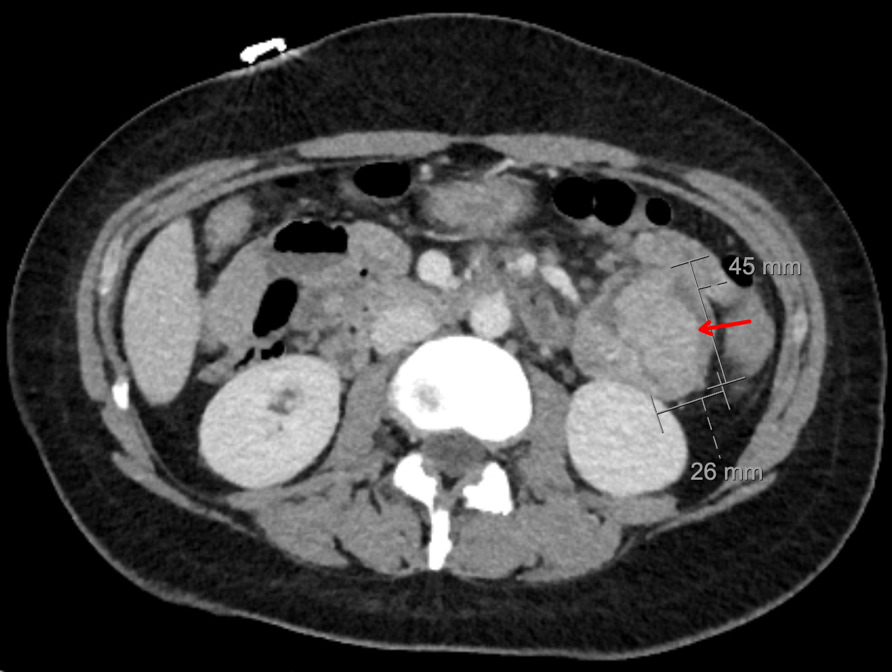

CT abdomen and pelvis with enterography showed numerous intraluminal small polyps in the jejunum largest measuring up to 4.5 x 2.6 cm, 3.0 cm polyp in the left lower abdomen, short segment small bowel intussusception with a polyp as lead point in the right abdomen without associated bowel obstruction or inflammatory bowel thickening, reactive mesenteric lymph nodes and splenomegaly (14.8 cm) (Figure 2). Esophagogastroduodenoscopy and colonoscopy were done, which showed few sessile and semi-pedunculated polyps measuring 4 - 10 mm in the ascending, transverse, descending, and sigmoid colon, multiple large polyps (sessile, semi-pedunculated, and pedunculated) measuring 6 - 20 mm in the rectum, multiple 3 to 8 mm sessile polyps in the gastric fundus and gastric body and a single 15 mm pedunculated polyp at the pylorus. There was no bleeding, and no stigmata of recent bleeding. Polypectomy of a pyloric polyp was done, and histopathology showed features of a hamartomatous polyp with arborizing compact bundles of smooth muscle (Figure 3). Genetic testing was positive for a heterozygous pathogenic variant [c.256C>T (p.R86*)] in the Serine/threonine kinase 11 (STK11/LKB1) gene, establishing the diagnosis of Peutz-Jeghers syndrome (PJS). She mentioned that her parents had screening colonoscopies, which were normal, and denied any family history of PJS. After 5 days of hospitalization, her hemoglobin level remained stable, and there were no overt signs of bleeding. Hence, she was discharged on ferrous fumarate 325mg every other day, ascorbic acid 500 mg twice daily, and folic acid 1 mg daily. Her hemoglobin at discharge was 5.0 g/dL, improved to 10.9 g/dL at 4 weeks, and to 14.0 g/dL at the 4-month follow-up.